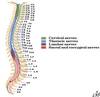

How many vertebra are there?

How many at each level?

7C, 12T, 5L, 5S, 4C

Which segment of vertebral colum belong to primary / secondary curvatures

Primary: thoracic & sacral

Secondary: cervical & lumbar